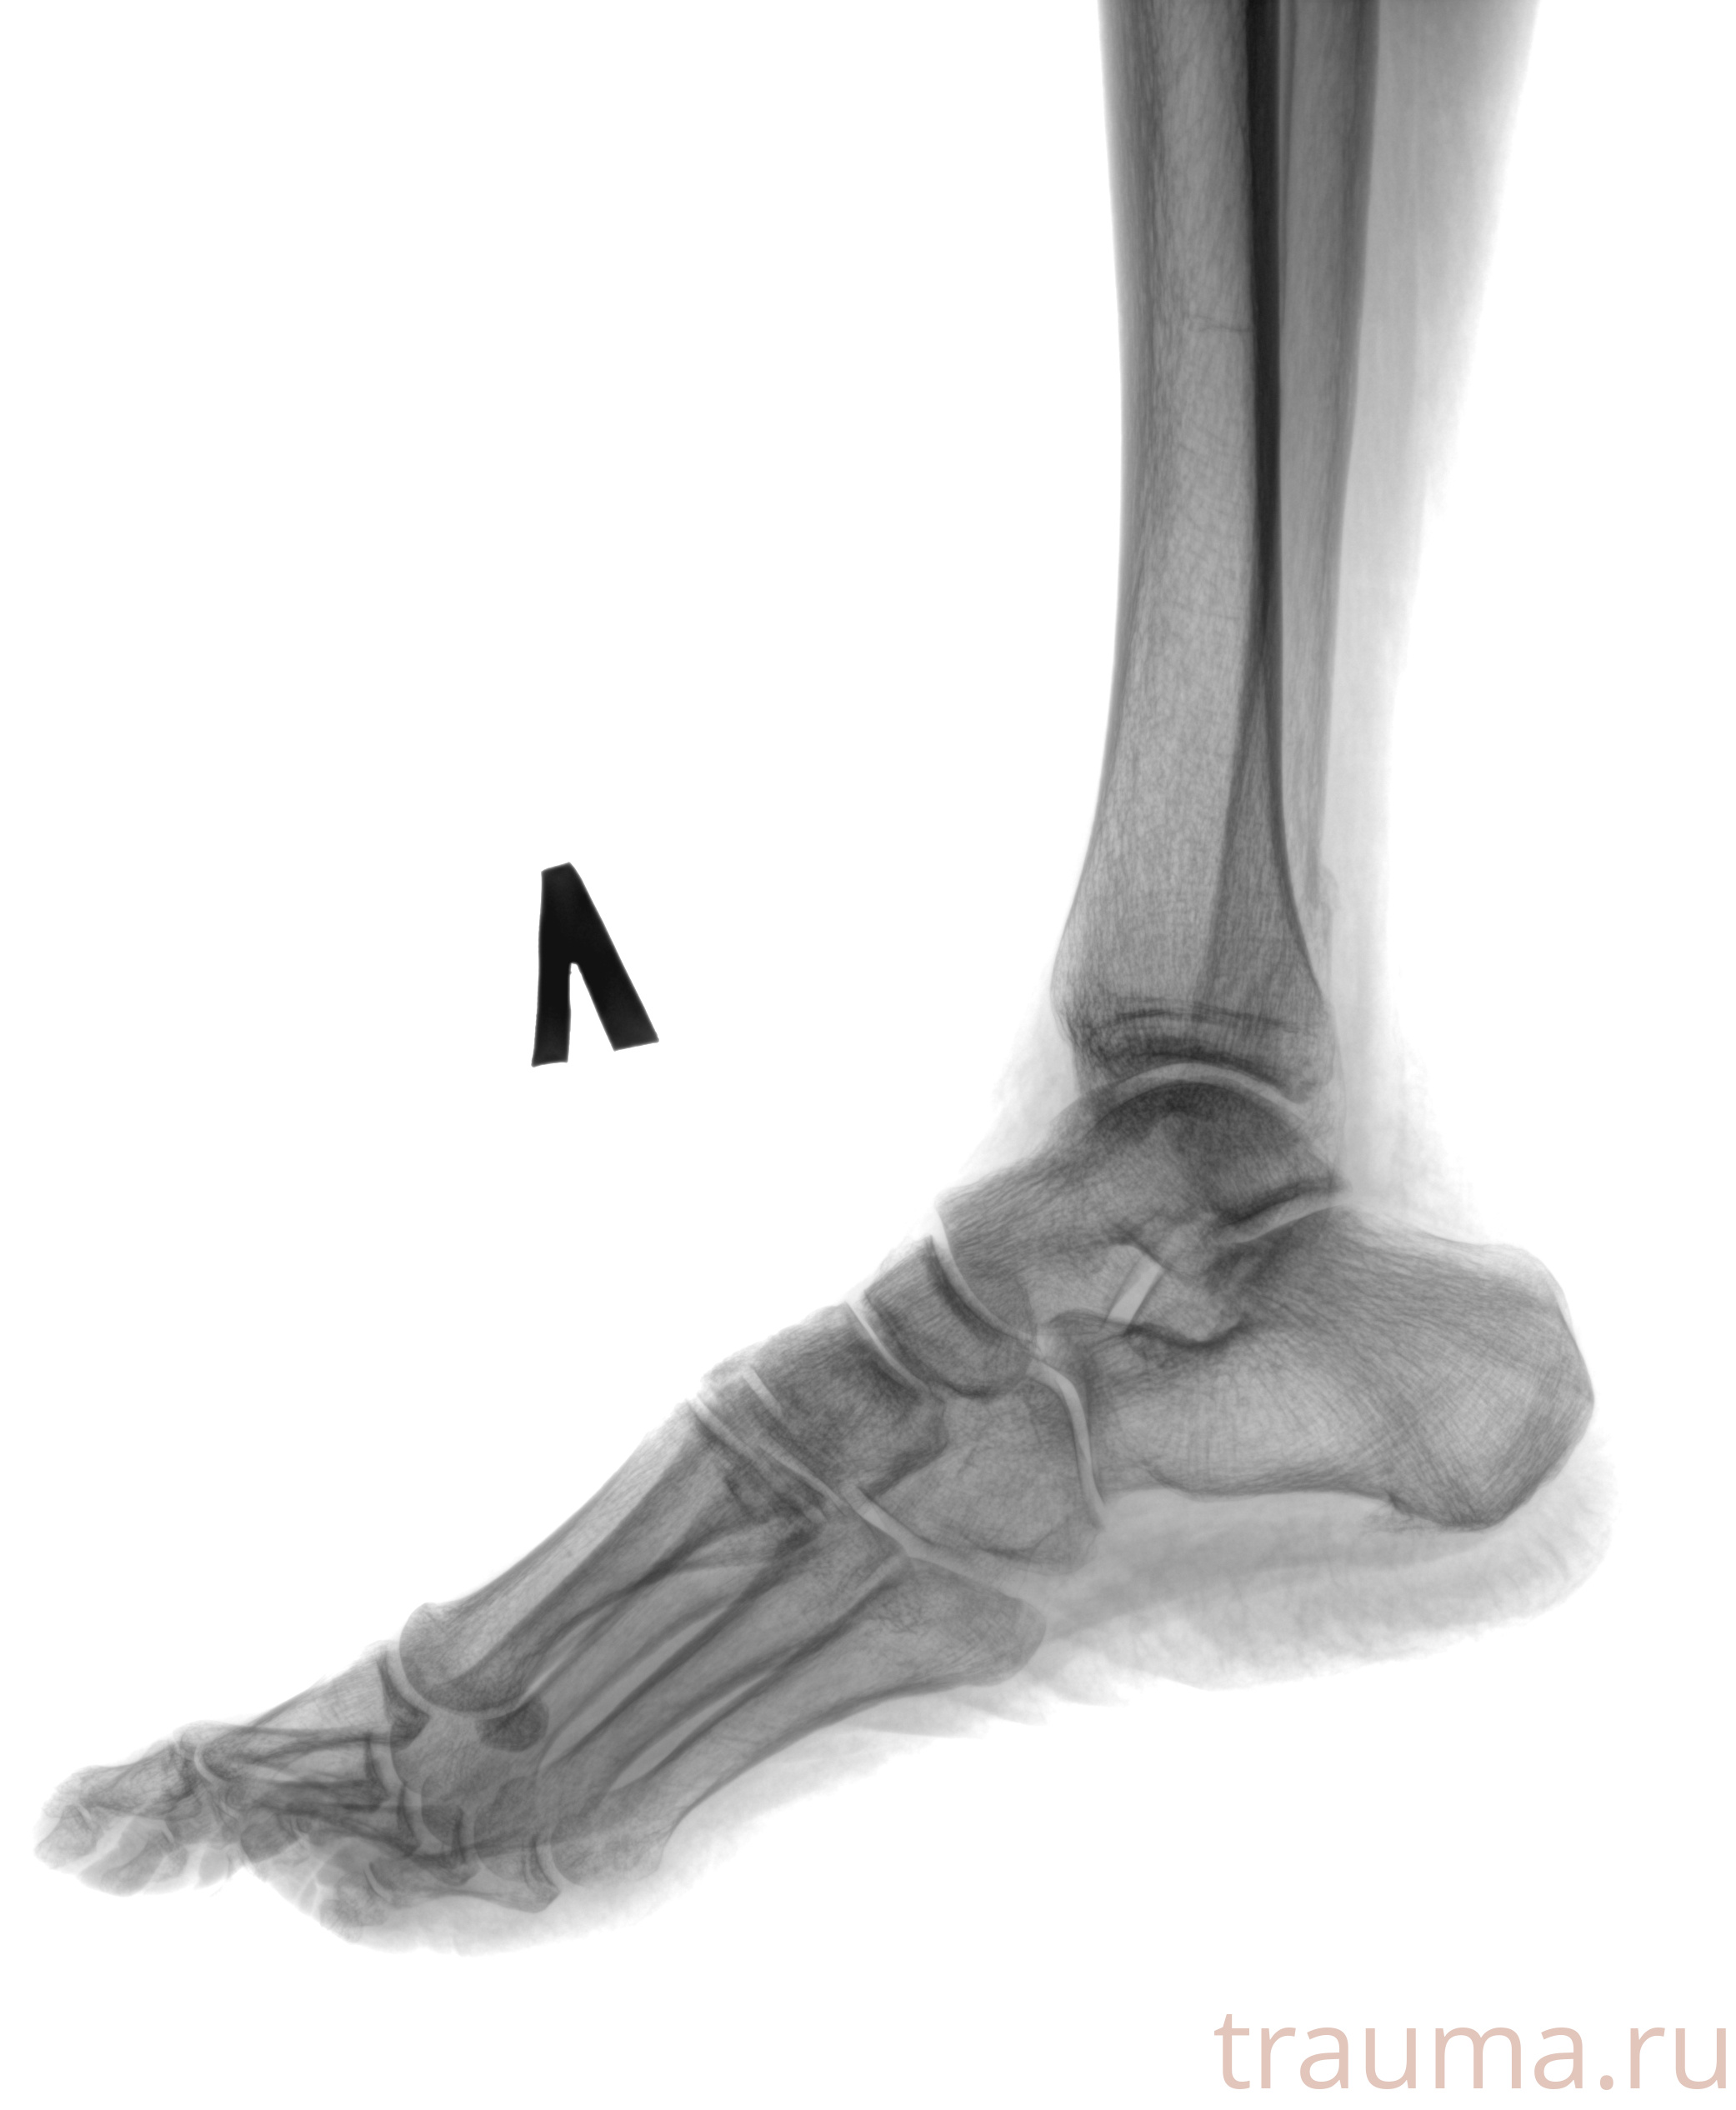

Рентгенограммы

Рентген на дому: по вашему адресу приезжает врач-рентгенолог, травматолог-ортопед с мобильным рентгеновским аппаратом, проводит диагностику травмы или заболевания, делает необходимые рентгенограммы, дает рекомендации по дальнейшему лечению. Получить качественные снимки в домашних условиях возможно благодаря уникальной методике, разработанной МосРентген Центром для института  Склифосовского